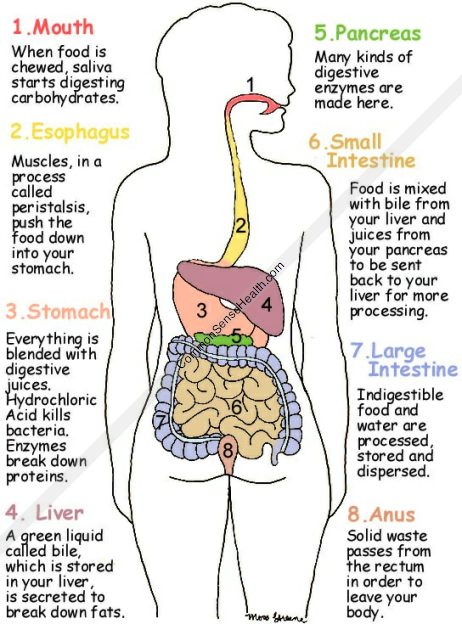

Digestion is the process by which food substances are broken down into simple and soluble form. All the parts of the body which work together to ensure digestion of food are called the digestive system.

PARTS OF THE DIGESTIVE SYSTEM

1. MOUTH:

The mouth takes in the food, the teeth chew the food, the food is mixed with saliva to soften it before it is swallowed. Enzyme in saliva called ptyalin digests carbohydrates into simple sugar. Proteins, fats and oil are not digested from the mouth, food is only masticated, mixed with saliva and swallowed.

2. GULLET:

The gullet is a long tube or passage way that connects the mouth to the stomach, it provides passage for food into the stomach but no digestion takes place in the gullet.

3. STOMACH:

The stomach is a sac-like organ that provides temporary storage for swallowed food. Carbohydrate is churned into chyme (semi fluid food), mixed with gastric juice, acidified and the bacteria in the food are killed. Proteins are also churned into chyme, and the enzyme called pepsin digests proteins into peptones. Enzyme called rennin changes fat in milk into semi solids.

4. SMALL INTESTINE:

The small intestine is a long narrow tube which is long as 8 metres. The small intestine has 3 components.

(1) Duodenum

(2) Jejunum

(3) Ileum

Carbohydrates, proteins, fats and oil acidity is neutralized. Carbohydrates and proteins are turned into semi fluid called chyme while fats and oil are emulsified (changed to droplets).

Carbohydrates are finally digested into simple sugars and are absorbed into the blood stream and circulated. Proteins are finally digested from peptones into amino acids, absorbed and circulated. Emulsified fats and oil are digested into fatty acid and glycerol, absorbed into the blood stream and circulated.

Digestion is the process by which food substances are broken down into simple and soluble form. All the parts of the body which work together to ensure digestion of food are called the digestive system.

PARTS OF THE DIGESTIVE SYSTEM

1. MOUTH:

The mouth takes in the food, the teeth chew the food, the food is mixed with saliva to soften it before it is swallowed. Enzyme in saliva called ptyalin digests carbohydrates into simple sugar. Proteins, fats and oil are not digested from the mouth, food is only masticated, mixed with saliva and swallowed.

2. GULLET:

The gullet is a long tube or passage way that connects the mouth to the stomach, it provides passage for food into the stomach but no digestion takes place in the gullet.

3. STOMACH:

The stomach is a sac-like organ that provides temporary storage for swallowed food. Carbohydrate is churned into chyme (semi fluid food), mixed with gastric juice, acidified and the bacteria in the food are killed. Proteins are also churned into chyme, and the enzyme called pepsin digests proteins into peptones. Enzyme called rennin changes fat in milk into semi solids.

4. SMALL INTESTINE:

The small intestine is a long narrow tube which is long as 8 metres. The small intestine has 3 components.

(1) Duodenum

(2) Jejunum

(3) Ileum

Carbohydrates, proteins, fats and oil acidity is neutralized. Carbohydrates and proteins are turned into semi fluid called chyme while fats and oil are emulsified (changed to droplets).

Carbohydrates are finally digested into simple sugars and are absorbed into the blood stream and circulated. Proteins are finally digested from peptones into amino acids, absorbed and circulated. Emulsified fats and oil are digested into fatty acid and glycerol, absorbed into the blood stream and circulated.